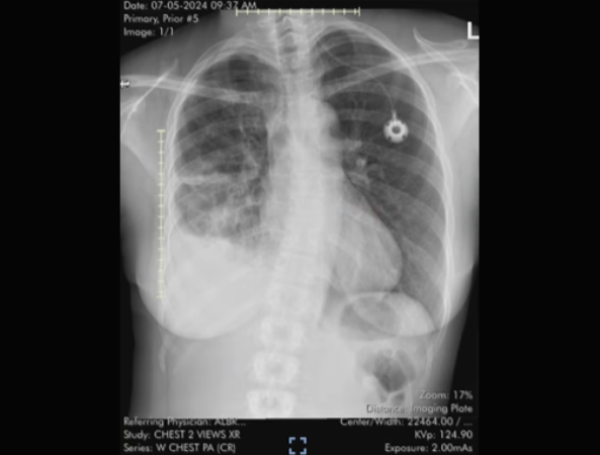

Los médicos pensaron que era un problema en el manguito rotador. Foto: Instagram: @savagelatinalungs / iStock

El diagnóstico de Reyna se tardó en llegar. Foto:Instagram: @savagelatinalungs

Cuando el especialista se percató que Reyna no mejoraba, la envió con un traumatólogo para realizar algunas radiografías que no revelaron ningún tipo de anomalía en el brazo de la paciente, por lo que creyeron pertinente remitirla con una fisioterapia que le ayudara a recuperar el movimiento y la funcionalidad.

Con la idea de que algo no estaba bien en su cuerpo y su estado de salud, la mujer agendó una cita con un neurólogo por iniciativa, en la que el médico sugirió hacer una resonancia magnética y algunas radiografías nuevas para descartar cualquier posibilidad.

Además, el especialista tomó en cuenta las sospechas que tenía Reyna, por lo que también le pidió que se sometiera a una tomografía computarizada de tórax. Tras varios exámenes, los resultados finalmente llegaron y revelaron que la paciente tenía cáncer de pulmón en etapa IV.